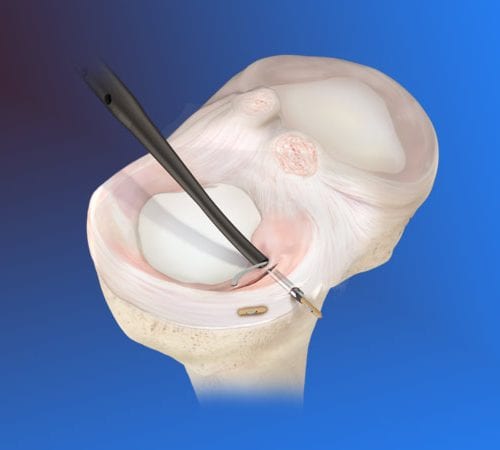

Diz Cerrahisi